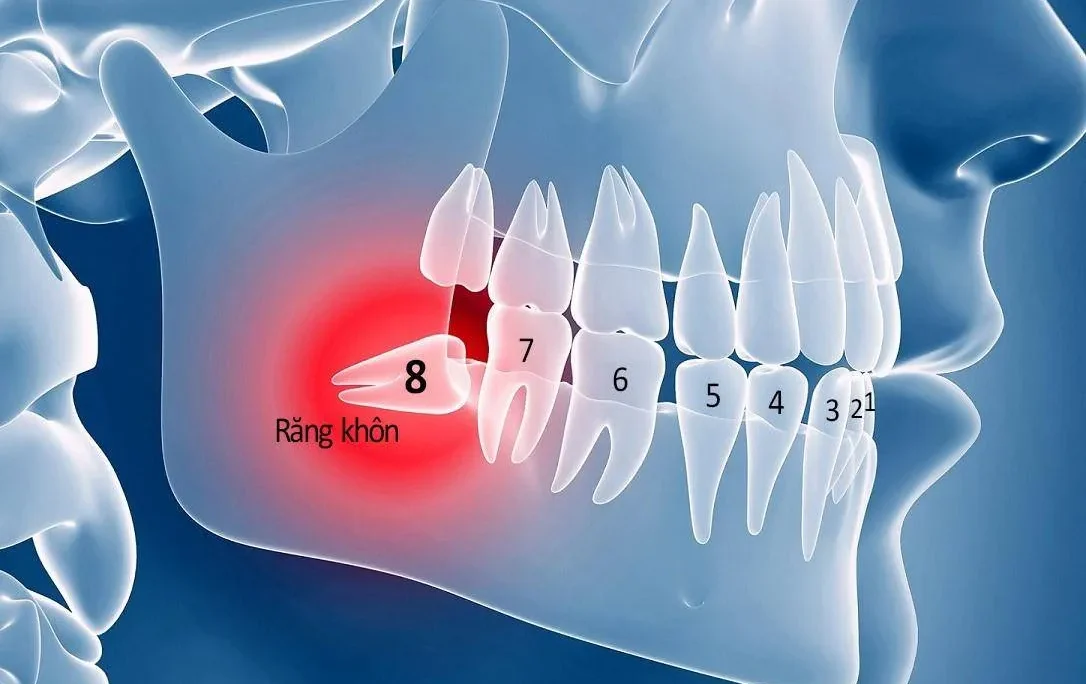

- Điều trị mọc răng khôn bị nứt lợi, sứng nướu